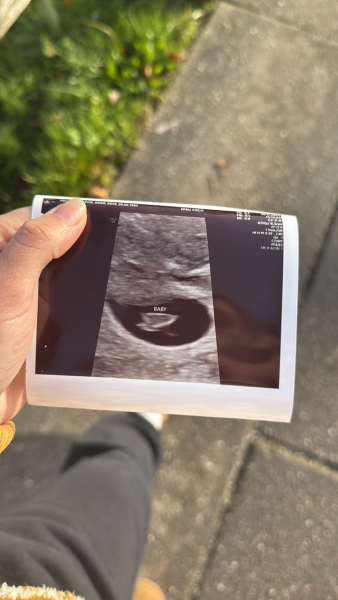

JDecember21 · 02/12/2024 12:52

@Runsandbuns omg so happy for you that’s amazing!!!! Really relieved for you :) 🩷🩷 you must feel so much better!!

@Brownbottle @sellingupslow

just to give you all an update.

just as I thought visibility was really poor once again due to the shape of my uterus and in the end we managed to see what we thought was a little flickering heart beat and obvs everything else.

However, there is now a 2nd gestational sack in there so there is a twin, but the visibility was so poor that we couldn’t really see what was in there…. So I need to go back in 10 days to see if the 2nd baby is viable or not!

but was nice to see the little flickering heart beat but again it wasn’t very clear which is a shame so we can’t say with certainty that everything is ok but we saw the outline of everything I think it’s just my shape is very hard to see.

head is a little bit all over the place but staying strong !! Pray for twin number 2!! Xx

@Runsandbuns so pleased for you, lovely scan image and great you can see heartbeat!

@JDecember21 What a rollercoaster! Must be frustrating that poor visibility is meaning it’s hard to know exactly what’s going on but good to see the little heartbeat! What a surprise on the twin - will cross everything for you and hope it is viable Flowers